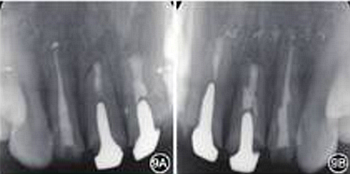

見圖8,圖9,圖10,圖11。分別于術(shù)后3、6個(gè)月時(shí)復(fù)查根尖X線片,8個(gè)月時(shí)復(fù)查錐形束CT并分別進(jìn)行臨床檢查。復(fù)查結(jié)果顯示根尖病變已愈合,根尖無明顯低密度影。臨床檢查叩診正常,無松動(dòng),牙齦位置無明顯變化。

圖9 6個(gè)月復(fù)查患者根尖X線片 A:根尖病變愈合;B:根尖病變接近愈合